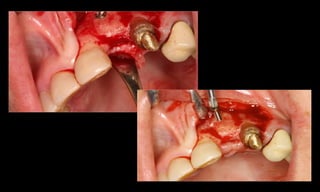

10-10-2005

Novembro de 2005

24-01-2006